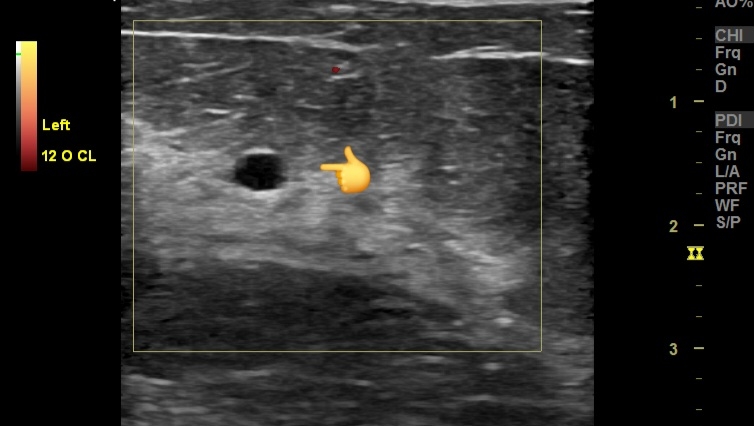

#Ultrasound Findings

- Seromas in the Breasts:

- Anechoic or hypoechoic fluid collections within the breast tissue.

- Well-defined margins.

- No internal vascularity.

- Posterior acoustic enhancement.